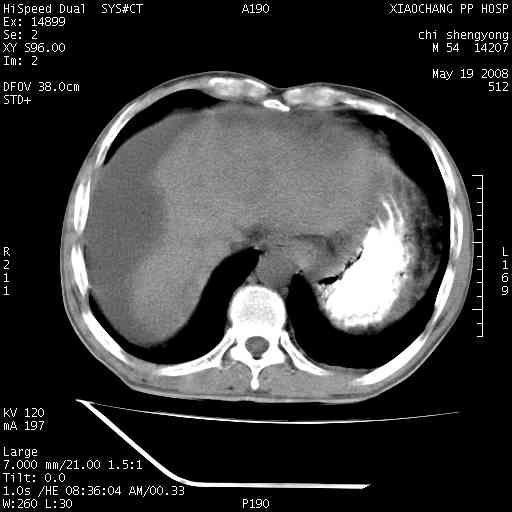

以下是引用zjzjr在2008-5-21 10:52:00的发言:[br]肝左叶巨块型肝癌伴门静脉左支瘤栓形成.肝硬化、腹水,胃底静脉曲张,脾术后改变。

以下是引用随光逐影在2008-5-21 16:20:00的发言:[br]1)肝左叶肝癌伴门静脉左支瘤栓形成,腹膜后淋巴结转移。2)肝硬化、腹水、胃底静脉曲张。3)胆囊炎。4)脾脏缺如,为切除术后所致。